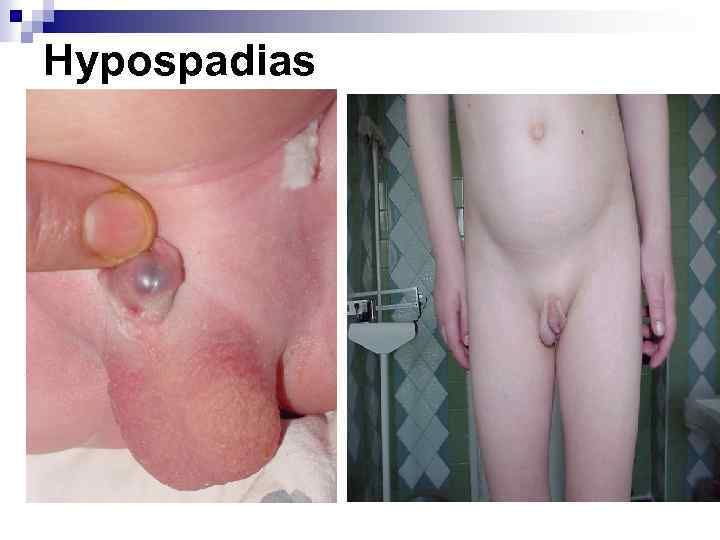

Hypospadias

Hypospadias

Hypospadias

Hypospadias